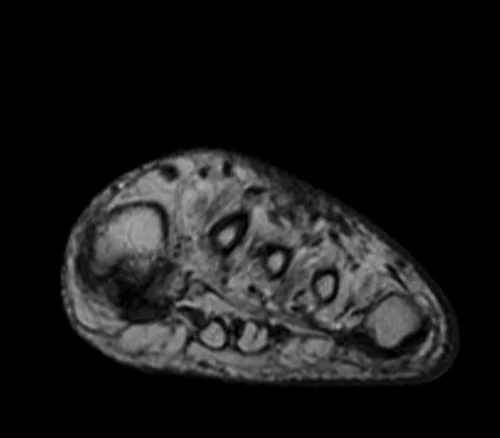

MRI FOOT AXIAL T1 IMAGE 1 - MRI